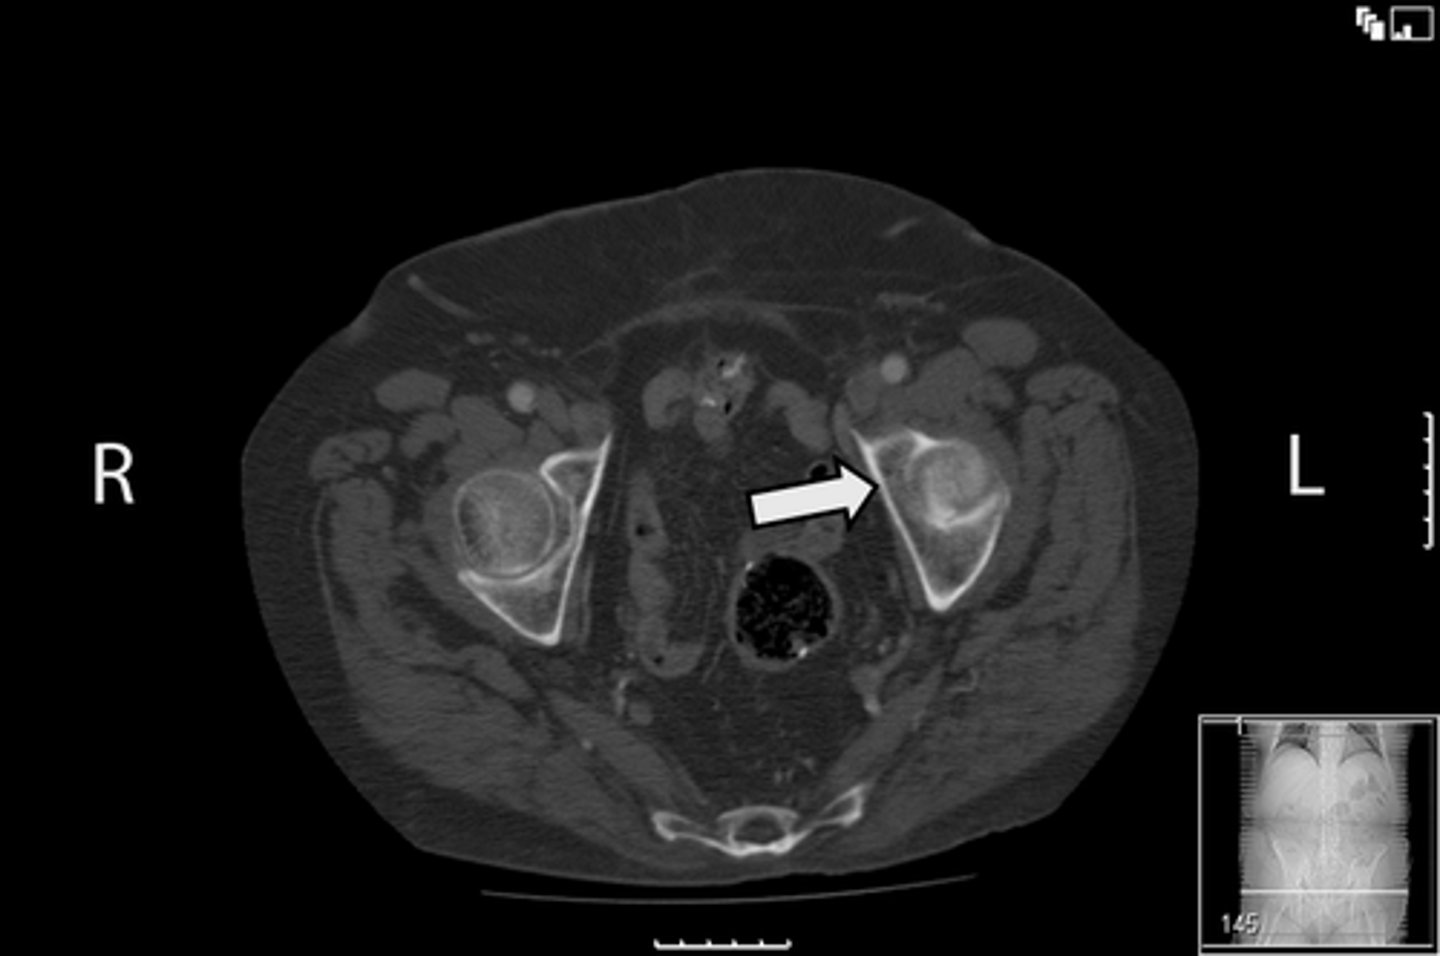

Axial male pelvis CT

What is the image?

Descending colon/sigmoid colon juncture

What is indicated in the image?

L external iliac artery

L gluteus muscle

L iliopsoas muscle

L internal iliac artery

Posterior aspect of L iliac bone

L sacroiliac joint

R common iliac artery

R gluteus muscle

R iliacus muscle

Posterior aspect of right iliac bone

R psoas muscle

R sacroiliac joint

R and L rectus abdominis